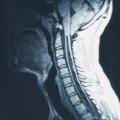

Syringomyélie

SYRINGOMYELIE